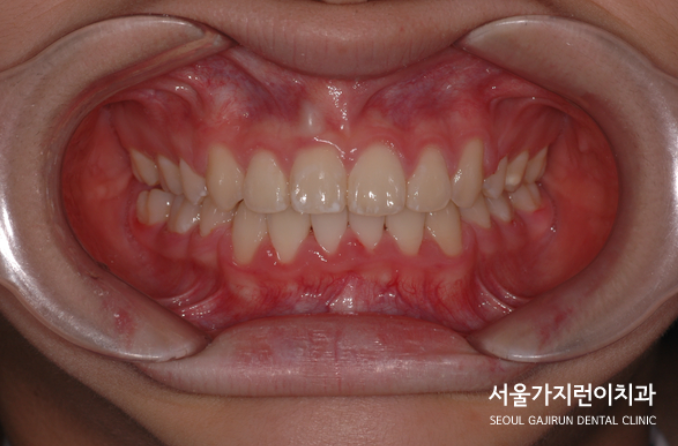

매복된 중절치 치료 결과

위 사진을 보면 달라진 모습을 확연하게 확인할 수 있었습니다. 치근 흡수 없이 가지런한 치아배열이 완성이 되었는데요. 비교적 8세의 나이에 일찍 발견하여 교정을 진행해 좋은 결과를 얻을 수 있었습니다. 만약 매복된 치아가 잇몸뼈와 유착이 심했다면 결국 치아가 내려오지 않았을 수도 있었는데요. 어린 나이에 발견해 유착 가능성이 낮은 탓에 온전한 자리를 찾아볼 수 있게 되었습니다. 상악 중절치와 매복을 비롯한 맹출 장애는 혼합치열기에 흔하게 발견할 수 있는데요. 유치 빠지고 영구치가 나는 시기에 교정치과를 찾아 검진해보면 바르게 성장하고 있는지를 체크할 수 있으니 성장기의 자녀가 있는 가족이라면 유심히 체크해보는 것도 좋겠습니다.